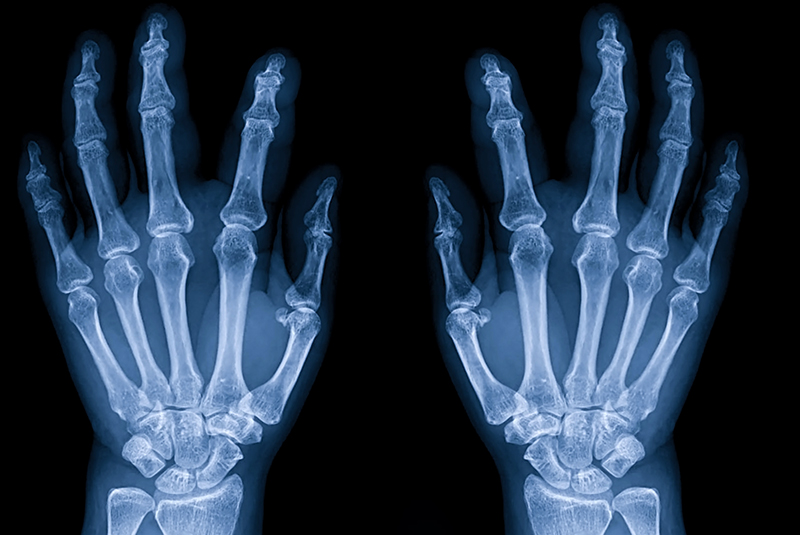

Expert Care for the Hand, Wrist,

and Upper Extremity

Capital Hand & Wrist Center provides specialized care for the full spectrum of hand, wrist, and upper extremity conditions. Whether caused by injury, overuse, or disease, these problems can impact your mobility, independence, and quality of life.